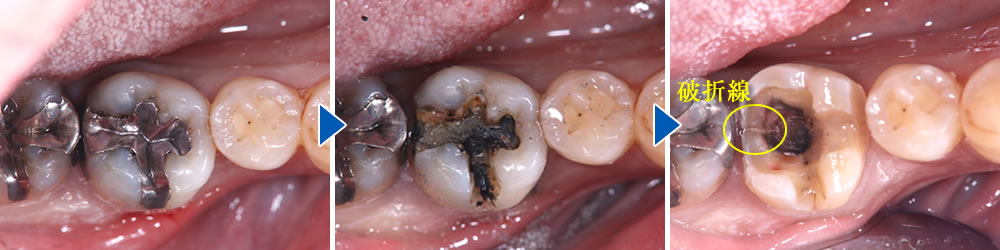

メタルインレーの除去

当該歯のメタルインレーを除去したところ、歯の内部に2次カリエス(虫歯の再発)を認めました。

う蝕検知液(虫歯部分に着色する薬液)を使用しながら、慎重に虫歯除去を行ったところ、遠心に歯根破折を確認しました。歯周ポケットが深かった部位と破折線が一致しており、このままつめ物を装着しても予後不良となる可能性があることを患者さまに説明したところ、抜歯とインプラントによる治療を希望されました。